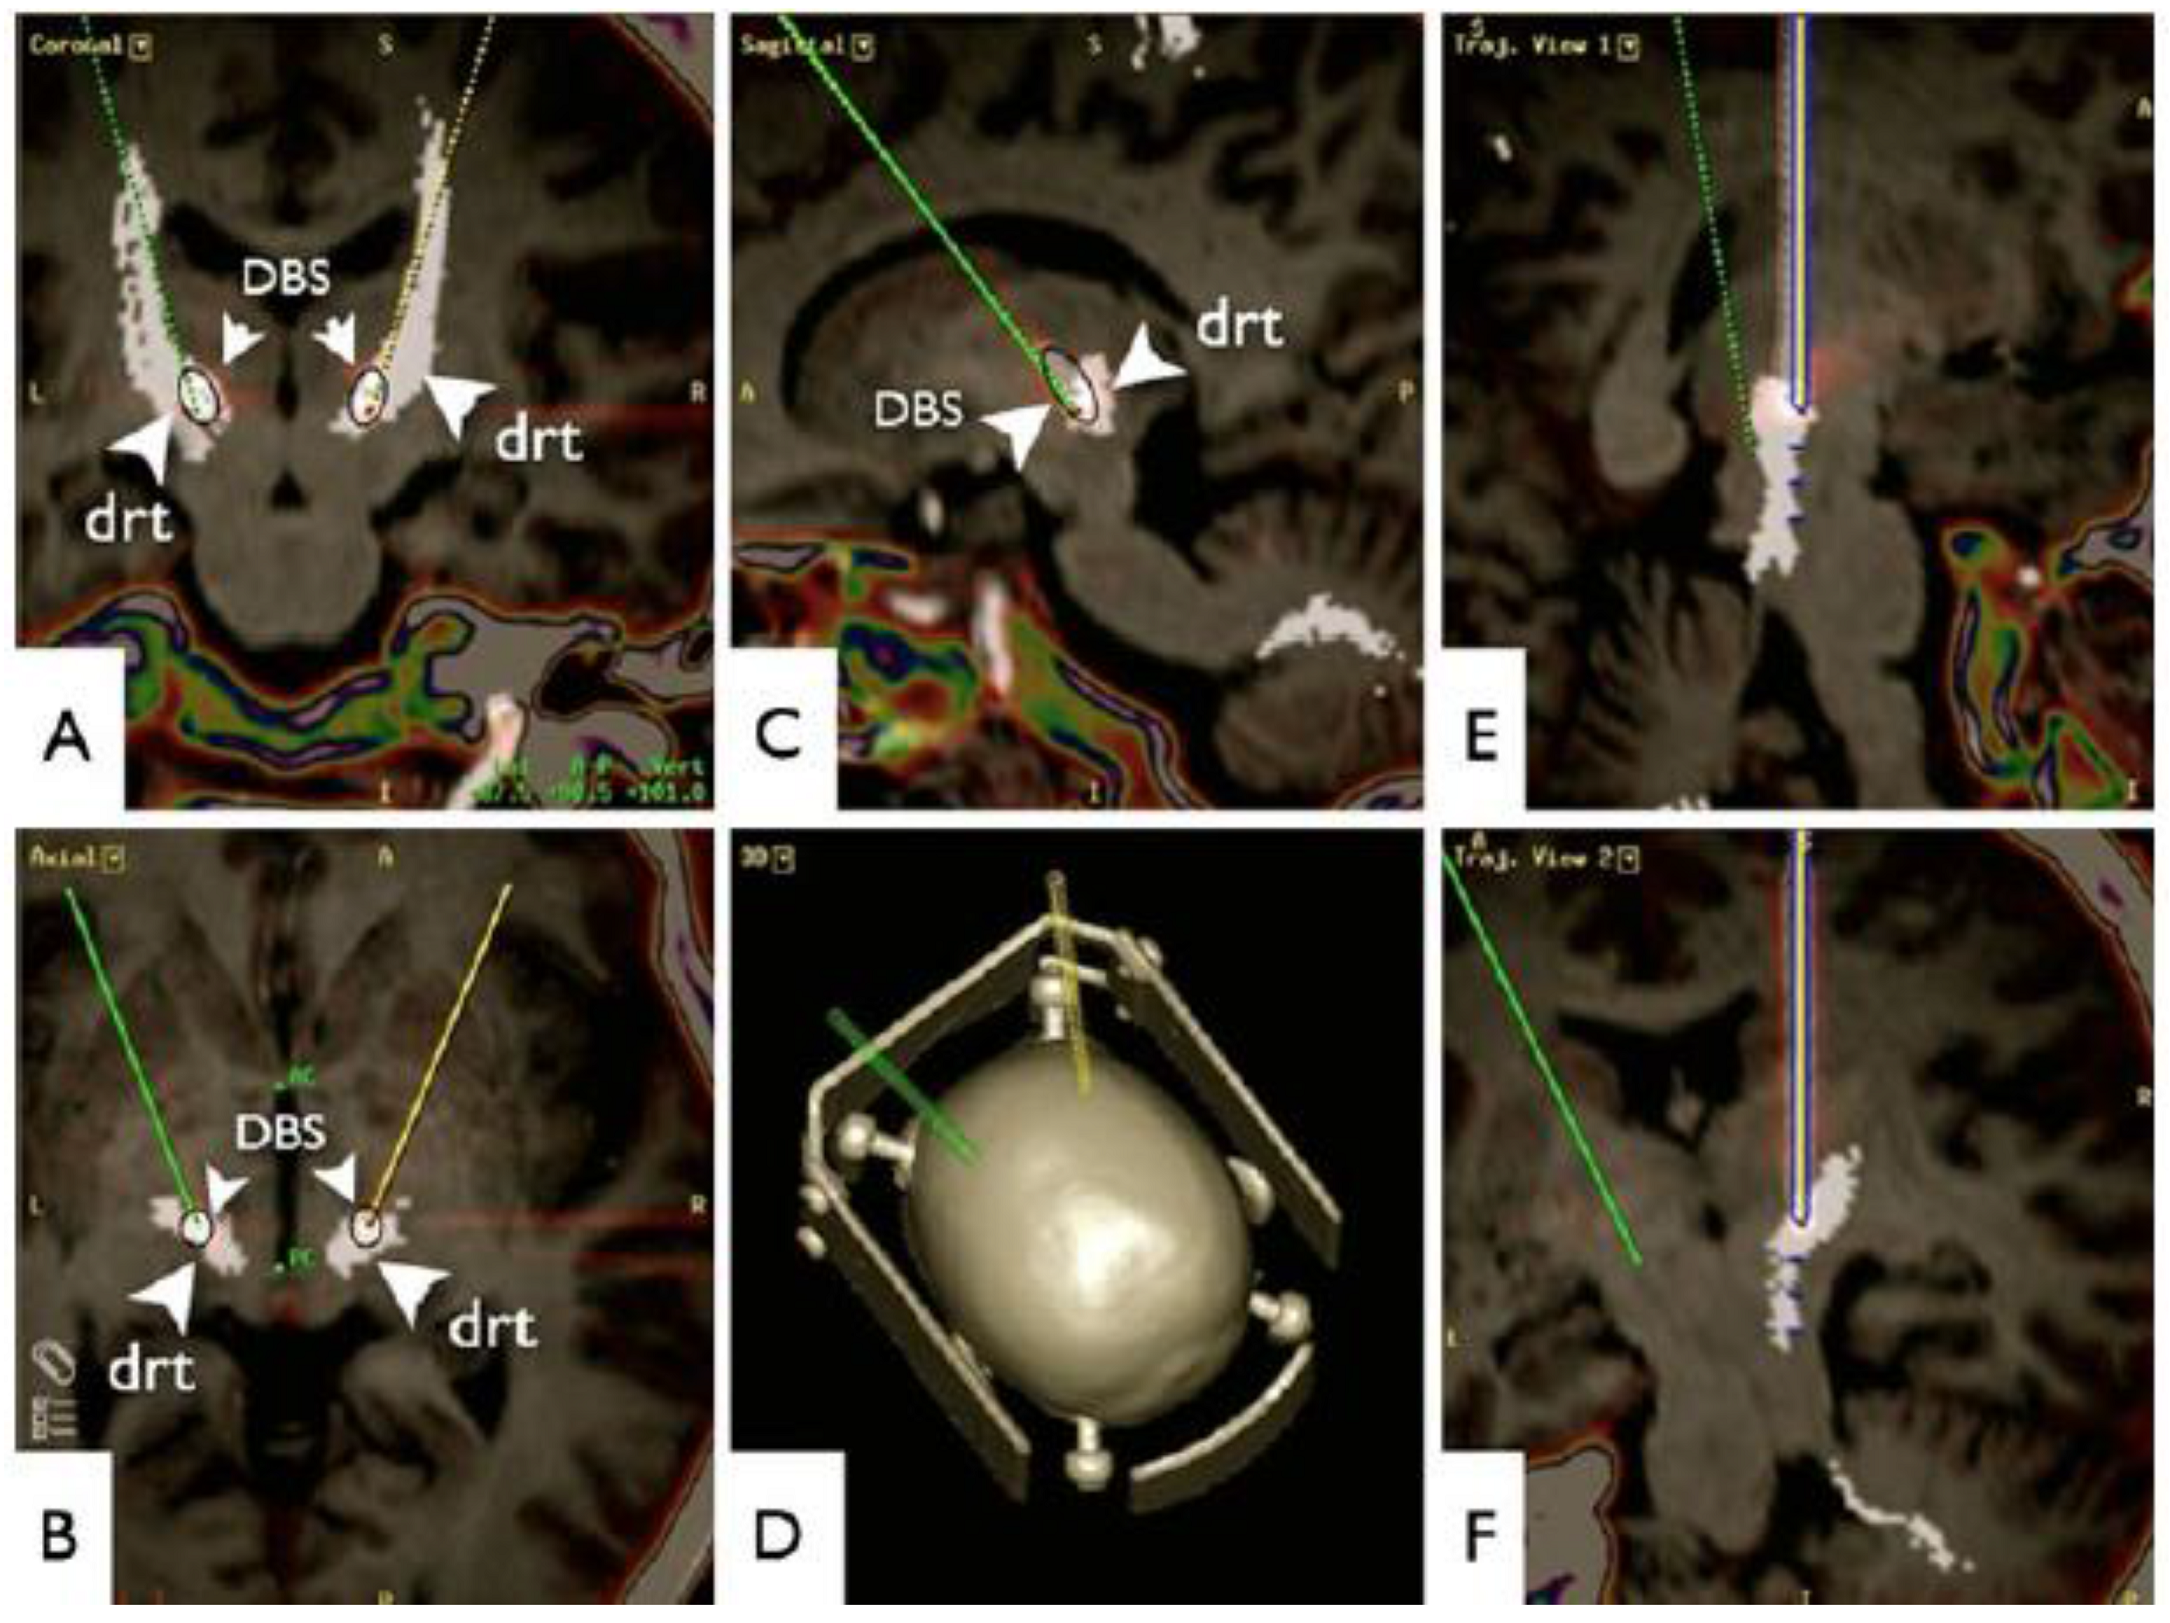

- Coenen, V.A.; Allert, N.; Madler, B. A role of diffusion tensor imaging fiber tracking in deep brain stimulation surgery: DBS of the dentato-rubro-thalamic tract (DRT) for the treatment of therapy-refractory tremor. Acta Neurochir. (Wien) 2011, 153, 1579–1585; discussion 1585. [Google Scholar] [CrossRef] [PubMed]

- Coenen, V.A.; Allert, N.; Paus, S.; Kronenburger, M.; Urbach, H.; Madler, B. Modulation of the cerebello-thalamo-cortical network in thalamic deep brain stimulation for tremor: A diffusion tensor imaging study. Neurosurgery 2014, 75, 657–669; discussion 669–670. [Google Scholar] [CrossRef] [PubMed]

- O’Halloran, R.L.; Chartrain, A.G.; Rasouli, J.J.; Ramdhani, R.A.; Kopell, B.H. Case Study of Image-Guided Deep Brain Stimulation: Magnetic Resonance Imaging-Based White Matter Tractography Shows Differences in Responders and Nonresponders. World Neurosurg. 2016, 96, 613.e9–613.e16. [Google Scholar] [CrossRef] [PubMed]

- Sajonz, B.E.; Amtage, F.; Reinacher, P.C.; Jenkner, C.; Piroth, T.; Kätzler, J.; Urbach, H.; Coenen, V.A. Deep Brain Stimulation for Tremor Tractographic Versus Traditional (DISTINCT): Study Protocol of a Randomized Controlled Feasibility Trial. JMIR Res. Protoc. 2016, 5, e244. [Google Scholar] [CrossRef] [PubMed]